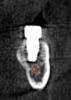

(4.) Digital plan of the virtual implant.

Figure 4

(5.) Digital plan of the virtual implant.

Figure 5

After a CBCT scan (Figure 3) and a digital impression were obtained for diagnosis and treatment planning, the DICOM file from the CBCT scan and the STL file from the digital impression were merged in a treatment planning software application for evaluation. A virtual crown was then created to facilitate a restoration-driven approach. The vital structures and osseous anatomy were identified, and the implant position was planned virtually (Figure 4 and Figure 5).